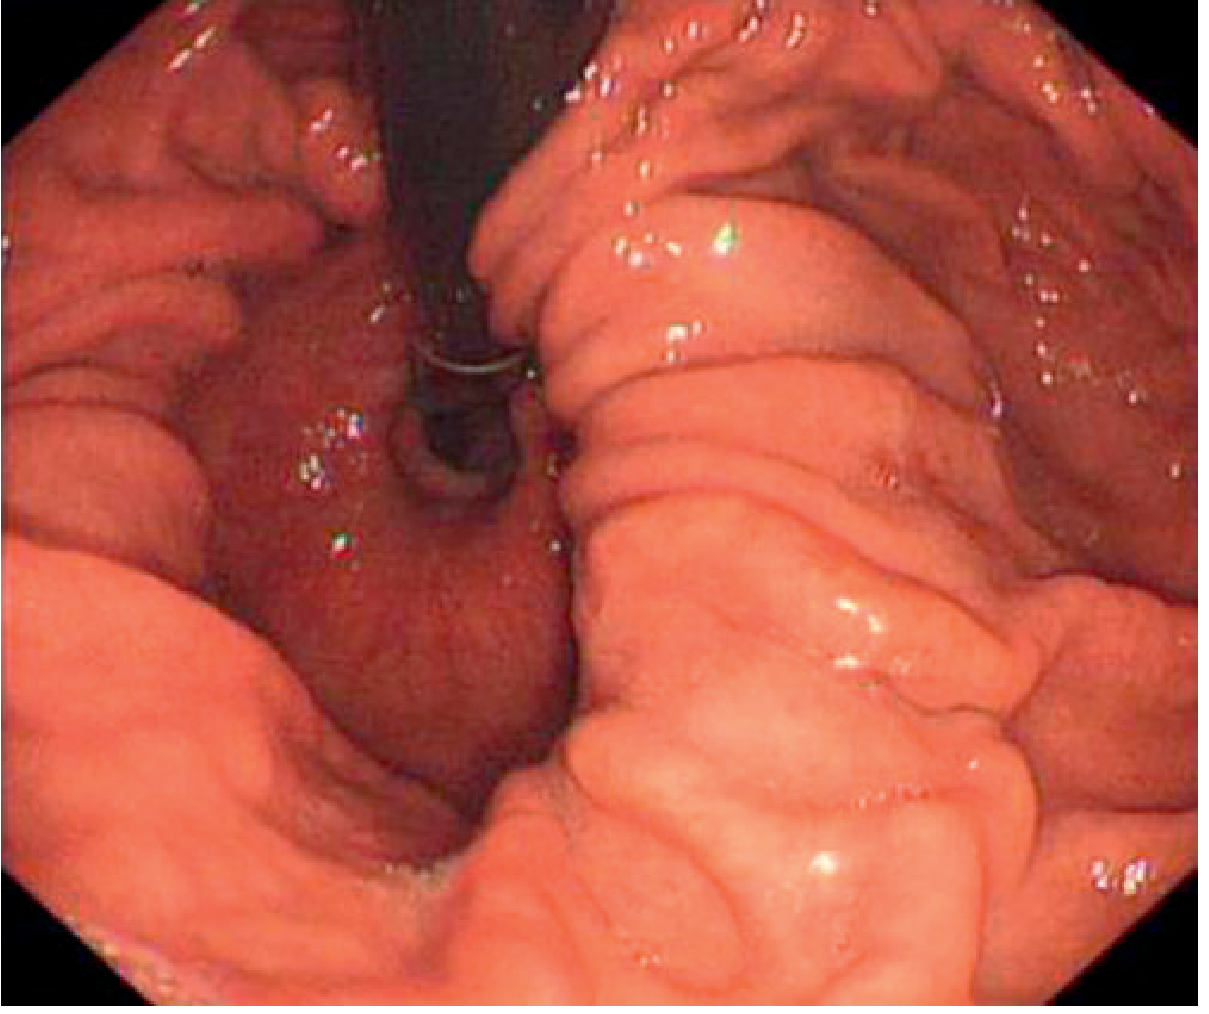

1. Endoscopy (OGD — Oesophagogastroduodenoscopy)

• Most accurate for identifying mucosal complications: reflux oesophagitis, Barrett's oesophagus, Cameron ulcers, strictures

• Diagnostic finding: gastric rugae seen passing through the diaphragmatic hiatus; or oesophageal B ring (squamocolumnar junction) visualised above the diaphragm

Endoscopic view of hiatal hernia — gastric folds seen traversing the diaphragmatic hiatus

Endoscopic image showing gastric folds passing through the extrinsic narrowing of the diaphragmatic hiatus — Grainger & Allison's Diagnostic Radiology